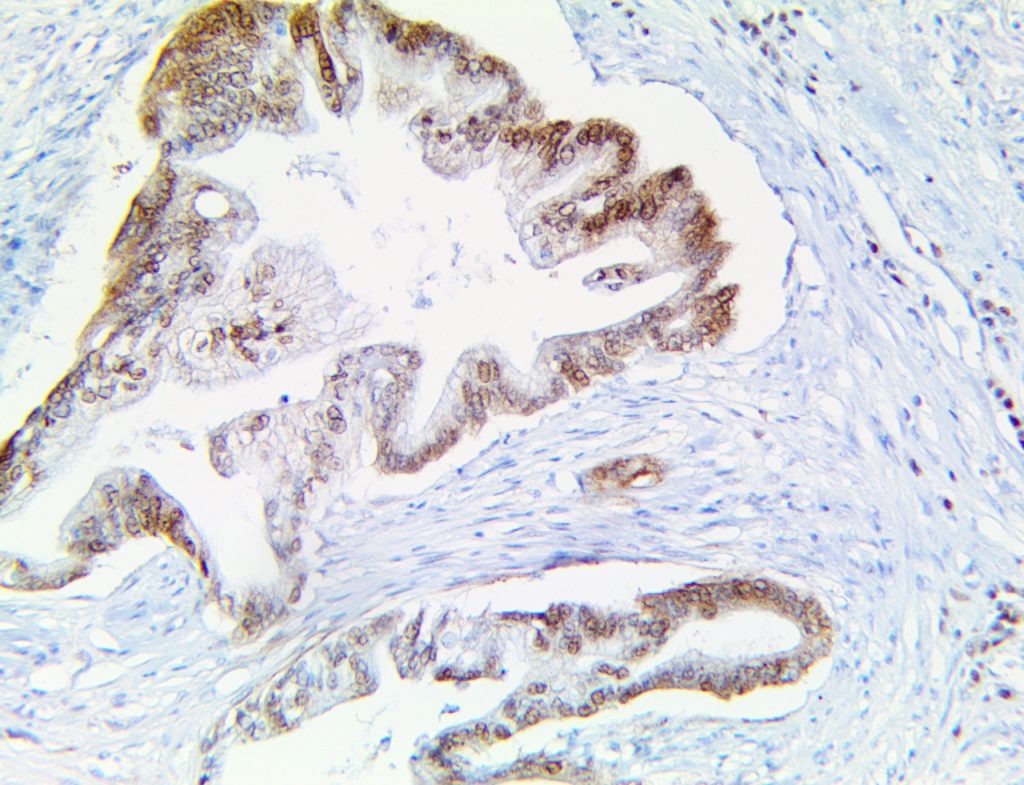

The first cytokines released are interleukin 1β (IL-1β) and tumor necrosis factor-α (TNF-α), which attract a variety of circulating white blood cells (WBCs) to the infection site, including neutrophils, monocytes, macrophages, and natural killer (NK) cells. This response, along with the antipathogenic chemicals released by these cells (i.e., complement), comprise the innate immune response. These cells directly attack the invading pathogen and also release additional cytokines, chief among them interleukin-1 and 6 (IL-6). IL-6 is essential for invoking the adaptive immune response, which calls T-cells, B-cells, and T helper (Th) cells to the infection site. IL-6 also stimulates further recruitment, proliferation and activation of macrophages.

This activation induces inflammatory monocytes to highly express IL-6, starting a localized and then systemic cascade effect that results in hyperproduction of IL-6, which accelerates the inflammatory process. Because IL-6 also increases vascular permeability, excessive levels cause blood vessels to become very leaky. This, along with clotting factors released from vascular endothelial cells, stimulates the coagulation cascade, resulting in microthrombosis (tiny clots), which leads to ischemia and tissue death of the kidney, intestines, heart, liver, brain and extremities.